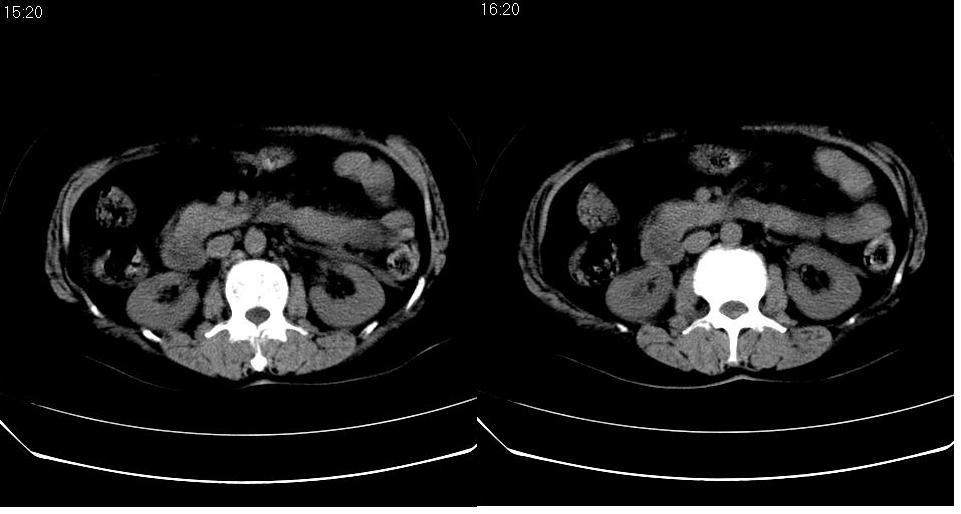

女 52岁,腹痛两天,无其它不适。

胆囊、胆总管结石,胰腺炎,少量腹水。

左肾周筋膜增厚,肾前间隙积液,胰腺肿大,胆囊结石,胰腺炎

支持:左肾周筋膜增厚,肾前间隙积液,胰腺肿大,胆囊结石,胰腺炎。

左肾周筋膜增厚,肾前间隙积液,胰腺肿大,胆囊结石,胰腺炎。

2、胆源性胰腺炎,诊断依据:同1外+左肾周筋膜增厚,肾前间隙积液,胰腺肿大。